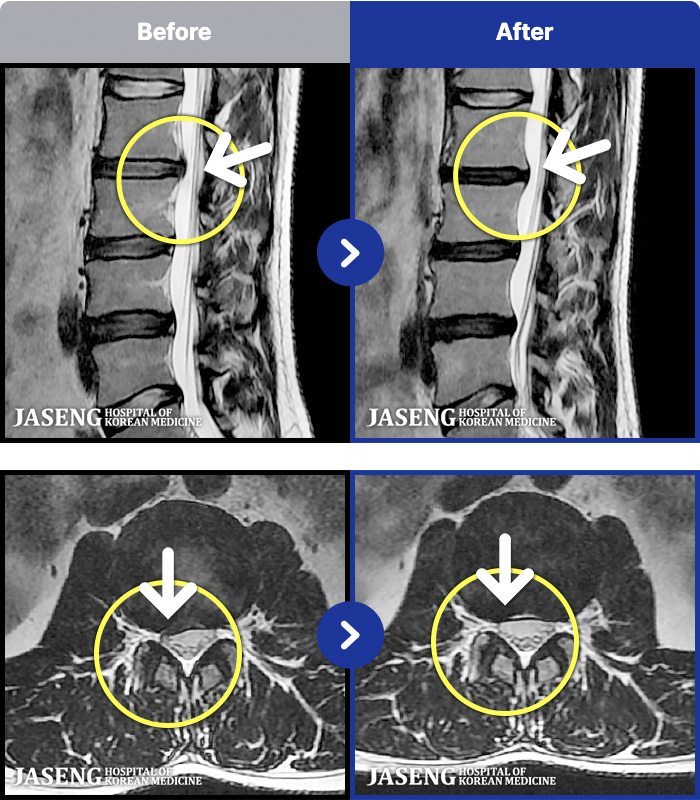

54 MRI ũ ʸ Ȯϼ.

[ϻ] 24.07.25~25.08.01